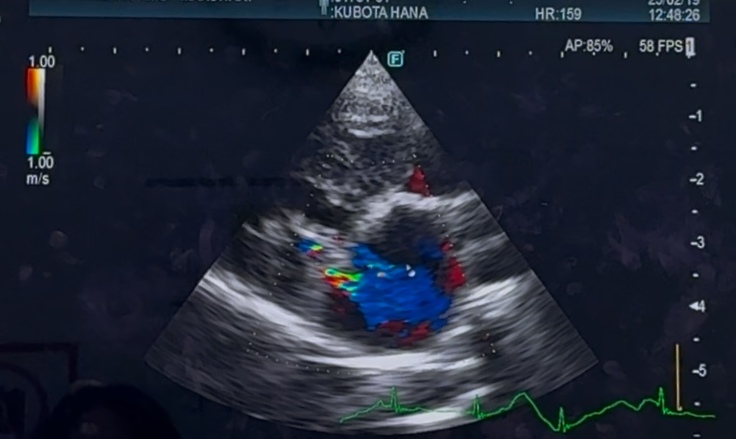

華の心臓は、術前、術後で

大きさはあまり変わっておらず

左心房の大きさは

今も、正常の倍はあり

逆流も、少し残っており…

右心の三尖弁逆流もあります

抗血栓薬を、今も飲み続けています